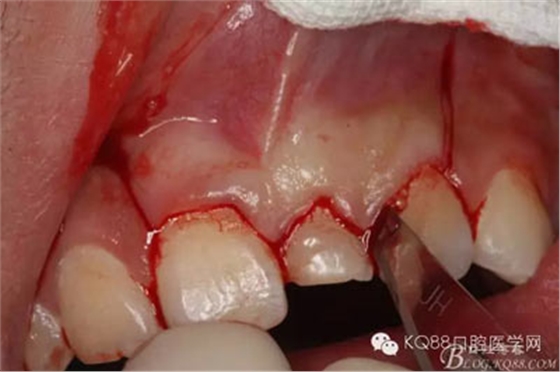

圖5.局部無痛麻醉下。行唇側(cè)齦溝內(nèi)切口

圖6.雙側(cè)垂直附加切口,形成梯形瓣